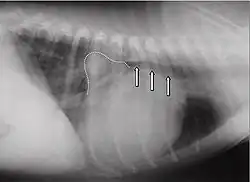

Les signes les plus fréquents d'une capacité cardiaque diminuée sont : la diminution des performances, la toux, les troubles nocturnes et la dyspnée. À l'auscultation, on[Qui ?] peut entendre dans la plupart des cas des bruits cardiaques holosystoliques d'intensité constante, de force des plus variables (degrés 1 à 6). Le bruit maximum de la valve mitrale (punctum maximum) est chez le chien dans le 5e espace intercostal, au niveau de la pointe du cœur. À la radio, un cœur dilaté peut être constaté. L'atrium gauche peut alors revêtir la forme d'un triangle (« triangle mitral ») décalé en direction caudo-dorsale. L'angle usuel entre les bronches et la colonne vertébrale peut disparaître en un trajet parallèle, et même l'atrium peut comprimer les bronches et l'irritation mécanique augmente alors les symptômes de toux. Dans les cas avancés, un œdème pulmonaire est diagnostiqué. L'électrocardiogramme est en général peu spécifique, il y a en partie des suggestions d'atrium dilaté (onde P allongée, au-delà de 0,04 s) ou d'un ventricule dilaté (complexe QRS plus long que 0,06 s). En outre, il peut y avoir des extrasystoles auriculaires ou ventriculaires, parfois une fibrillation auriculaire. Ce symptôme est fréquent chez les chiens avec une insuffisance mitrale fonctionnelle due à une cardiomyopathie dilatative. À l'échocardiographie Doppler, il est facile de reconnaître une insuffisance mitrale. Les autres conséquences qui surviennent sont : un élargissement du ventricule en raison de la surcharge en volume, souvent une hypercontractibilité en raison de mécanismes de compensation, et une oreillette substantiellement agrandie.